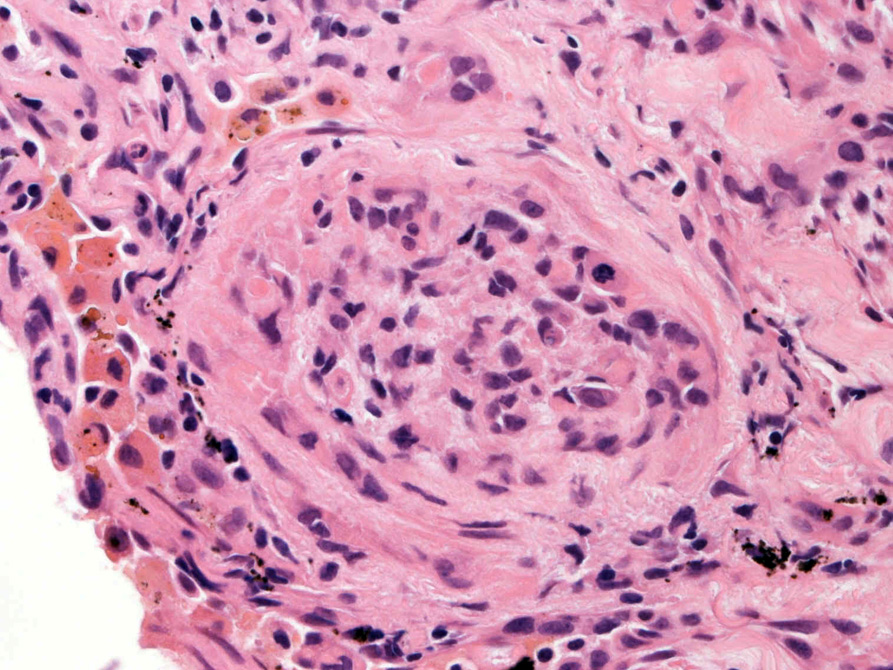

直径5-6mmの, 中央に弾性線維をふくむfibrous noduleがあり, 腫瘍細胞は結節の辺縁部に沿って認められる。

クリックすると大きな画像が見られます。

hyperchromaticな類円ないし多角の核で好酸性の広めの細胞質をもつ上皮様細胞が増殖している。右図では血管内を占拠するように腫瘍細胞が認められる。